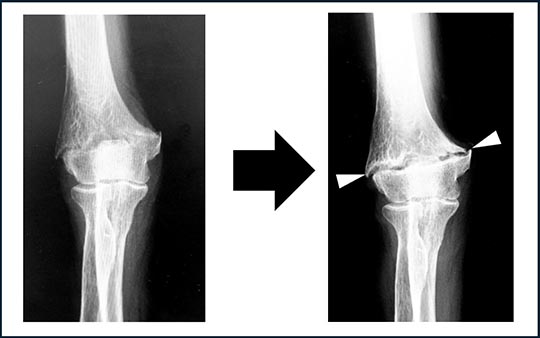

上腕骨小頭のみの骨折や上腕骨小頭と滑車の両方が骨折している場合があります(図4)。立った位置からの転倒など軽微な力で骨折することも多く、骨粗鬆症のある女性や高齢の方に多く発生します。上腕骨の関節面に、橈骨が突き上げるような外力が加わるため上方に転位(ズレ)していることが多く、ギプスで固定しても骨はつきません。

図4.上腕骨小頭・滑車骨折:レントゲン像で骨片(矢印)が上方に転位しています。